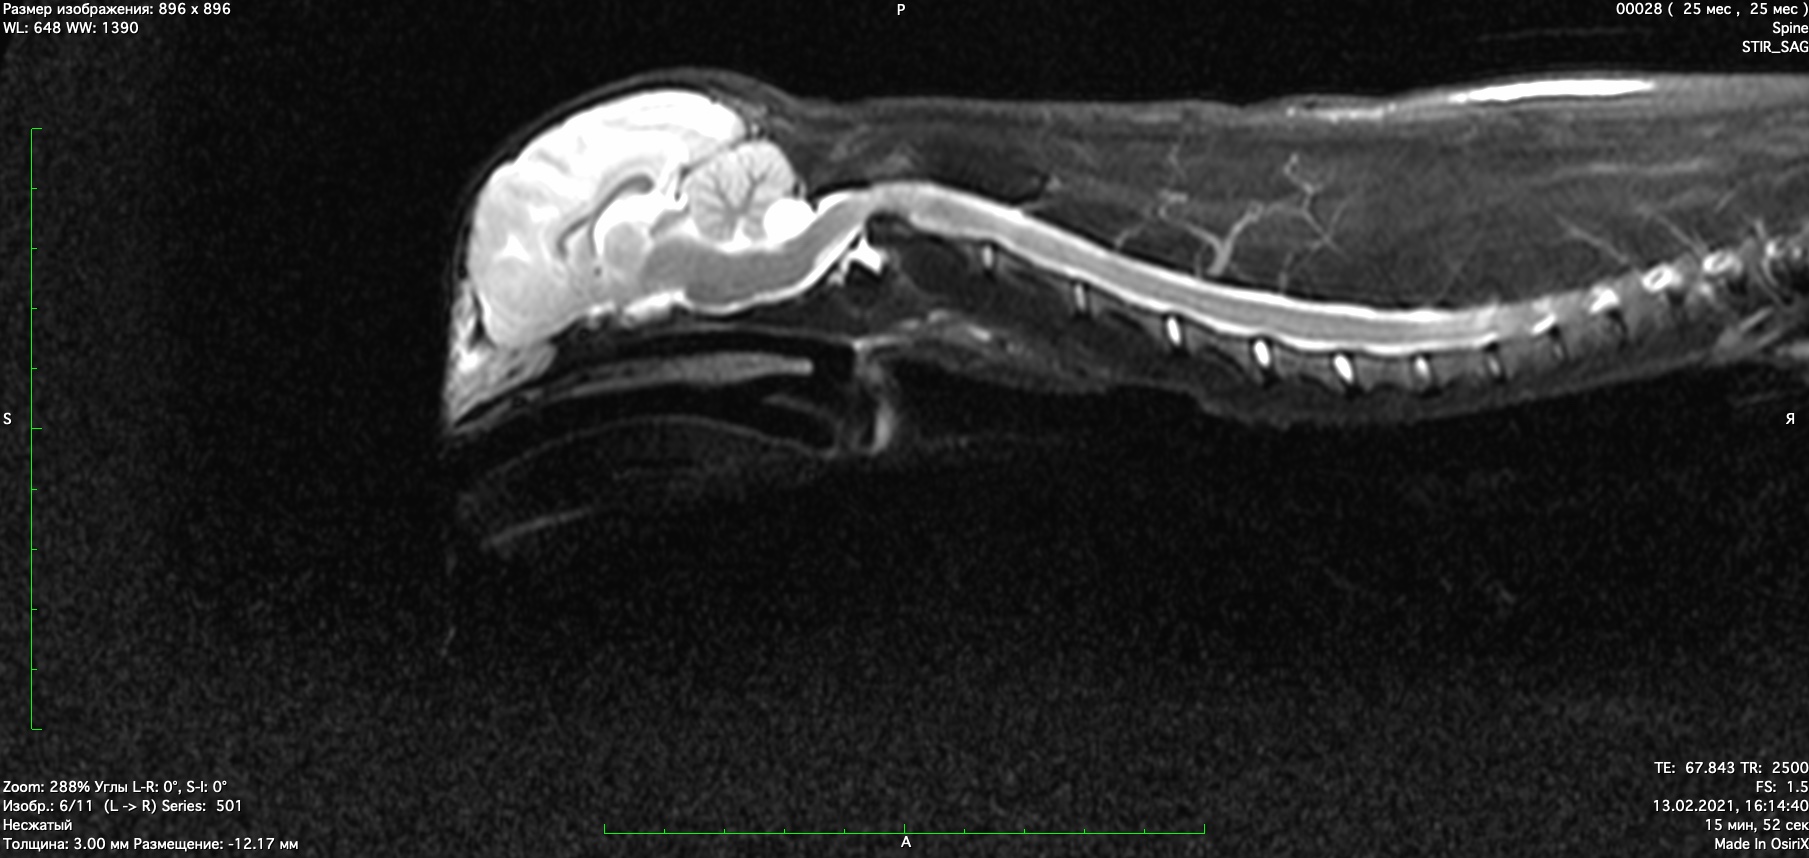

При проведении мрт диагностики установлено смещение второго шейного позвонка с компрессией спинного мозга, аплазия зуба второго шейного позвонка